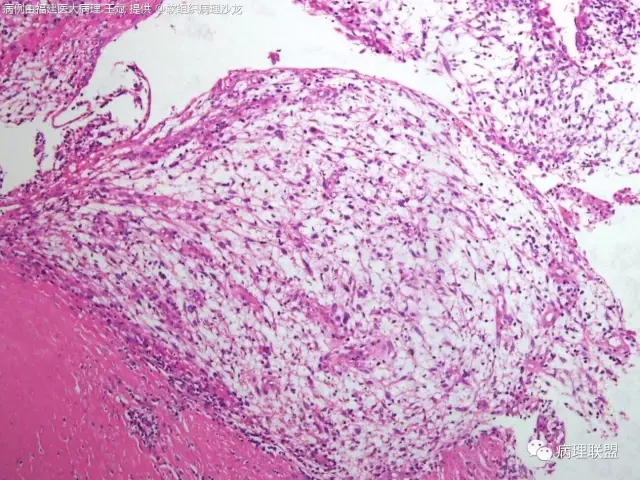

38岁,女性,手部小指背侧皮下肿物,3×2cm(病例由福建医大病理 王斌提供,致谢!)

是的,可以部分有粘液变,我见过的

血管瘤样纤维组织细胞瘤的肿瘤周围有淋巴细胞鞘,结节状分布,有假包膜,出血囊性变的为其主要特点,当然少数病例可以没有出血囊性变却出现粘液变。肿瘤细胞有一定异形性,属于低度恶性或交界性,最好做个FISH,看看有没有EWSR1-CREB1融合基因,刚查了一下,血管瘤样纤维组织细胞瘤还有另一种EWSR1-ATF1融合基因,无论是哪种,用EWSR1分离探针就可以检测